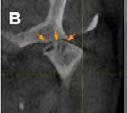

The pathway of a sinus tract that develops from a necrotic pulp is through the alveolar bone and emptying purulent exudate into the oral cavity. The stoma can be on the attached gingiva, alveolar mucosa or gingival sulcus. It can also empty on the buccal or lingual surface (Figures 1A, B). This is determined by the proximity of the apex to either the cortical plate and/or the density of the bone. Finally, it can also drain extraorally (cutaneous sinus tract) (Figures 2A, B).[3-5]

Figure 1B: Sinus tract was traced with size 35 gutta-percha. Periapical radiograph revealed origin of sinus tract was periapical lesion associated with distal root of first molar not second molar, indicating possibly wrong tooth had been treated. Figure 1A: Patient was referred to endodontist for evaluation because sinus opening had not healed after endodontic therapy on lower left second molar. Patient was asymptomatic and had been so prior to initiation of therapy; however treatment was initiated because of diagnosis of sinus tract opening facial to second molar

Figure 2B: By gently removing existing scab, sinus opening was evident. It was traced with size #25 gutta-percha cone to lower right central incisor that was unresponsive to cold and EPT. Figure 2A: Patient reported to clinic with history of persistent “pimple” on her chin. Plastic surgeon had excised pimple, but it reappeared within few weeks. fistula is lined with epithelium that may or may not be filled by granulomatous tissue.[22-26]